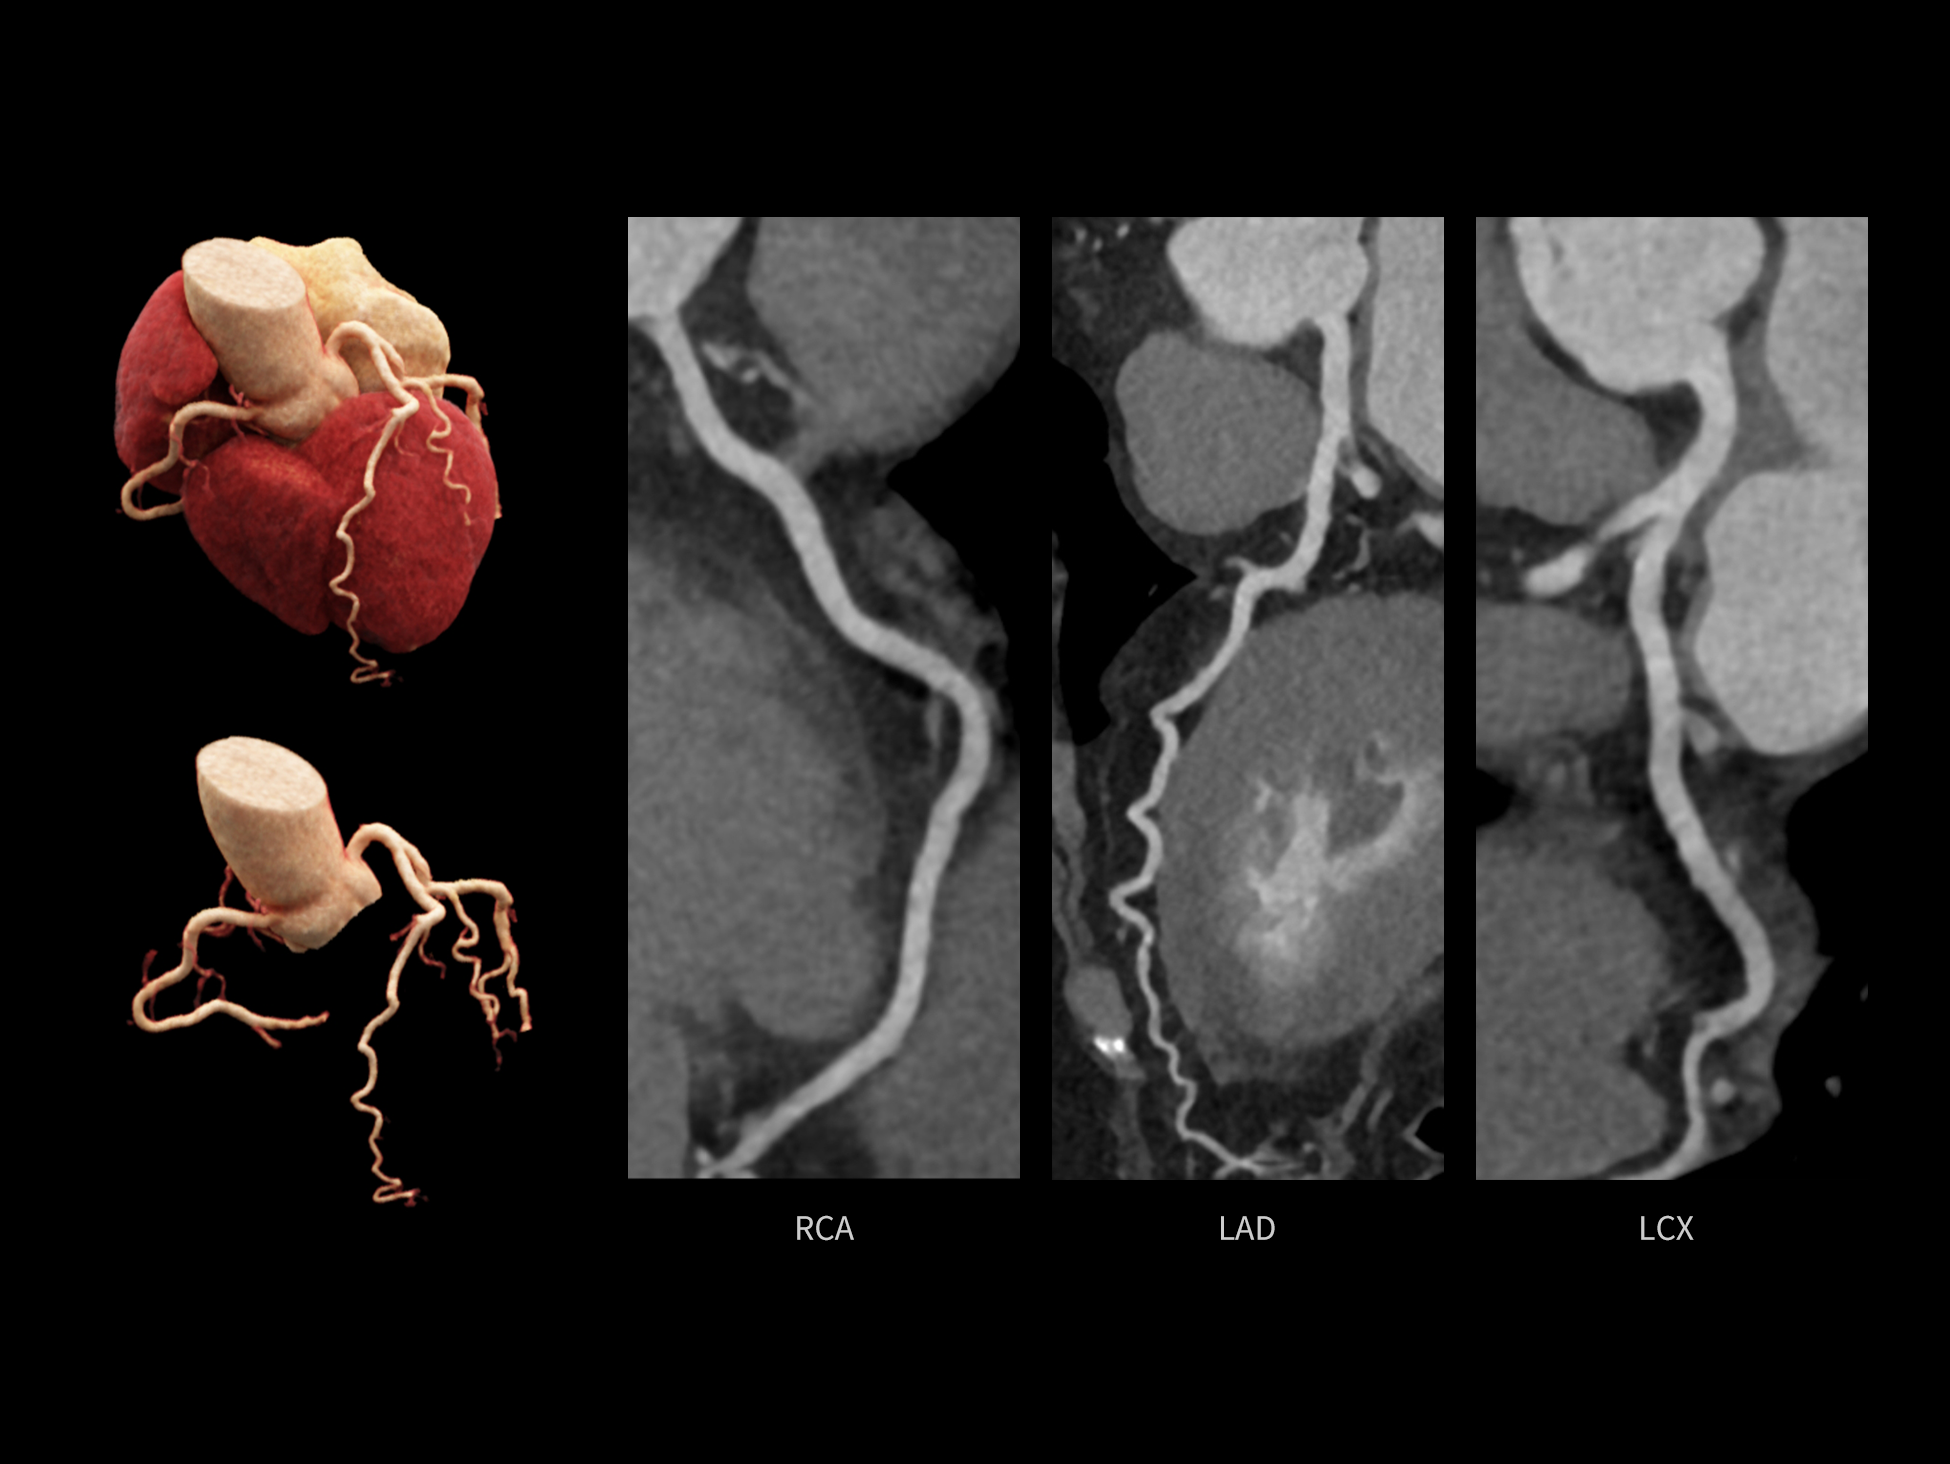

全时心脏

uCT SiriuX® 挑战心脏成像时间分辨率的极限,精准捕捉心脏全周期的动态变化。无论静态解剖形态,还是动态功能表现,都能清晰呈现,让心脏不再是“定格”的器官,而成为可视的生命律动。

CardioCapture 2.0 通过“识别–追踪–建模–校正”的完整流程,精准分割心脏结构,动态追踪运动轨迹,并构建多时相运动场,最终实现冠脉、瓣膜、心肌及心室结构的同步校正,清晰洞见每一次心跳细微变化,真正将心脏动态掌握于毫秒之间。

CardioCapture 2.0 在目标时相前后重建多时相影像,通过深度学习网络精准提取冠脉中心线,进而建立时相间运动模型,实现对冠脉分段图像的精准运动校正。

冠脉运动校正